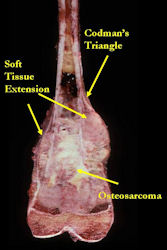

Gross Pathology: Conventional Osteosarcoma

These are examples of the gross pathology specimens of resected conventional osteosarcoma, consisting of both bony and soft tissue areas. X-rays of the specimens are included.

- Osteosarcomas are composed of ossified or non-ossified tissue

- Ossified tissue is yellow-white and hard

- Less ossified tissue is soft and less yellow

- Non-ossified tissue is tan and fleshy

- Most (95%) of conventional osteosarcomas penetrate the cortex and form a large extraosseous soft tissue mass

- The lesion permeates the marrow spaces

- Osteosarcomas usually infiltrate the marrow several centimeters away from the main tumor mass

- Skip lesions may be apparent that are separated from the main tumor by normal marrow

- Osteosarcomas may also have cartilaginous components that appear as translucent lobules, and/or fibrous components that are tan, soft to firm rubbery areas

- Osteoblastic areas are usually white to yellow, firm, hard and gritty

- The consistency of the tumor depends on the amount of osteoid deposition, cartilaginous and fibrous areas

- Foci of hemorrhage and necrosis are common

- Periosteal reactions such as the Codman’s triangle are apparent at periphery of soft tissue mass

- Osteosarcomas rarely penetrate the growth plate grossly

- Invasion of the joint is uncommon but can occur by cortical penetration, joint capsule extension, or extension along cruciate ligaments